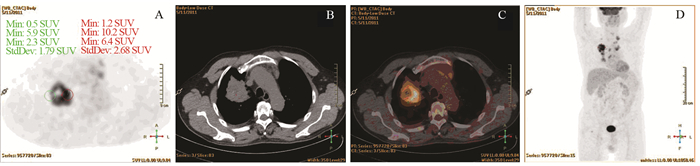

肺癌组P/D>1者占91.5%(65/71),炎性病变组P/D<1者占80.6%(25/31),两组差异有统计学意义(P<0.001)。以P/D>1为标准,对肺癌诊断的敏感度为91.5%,特异性为80.6%,准确性88.2%,见表 1,图 2~3。

![]() 图 2 一例典型的肺癌PET/CT图像Figure 2 PET/CT image of one typical case of lung cancerPatient, male, 67 years old. A moderately differentiated adenocarcinoma on the upper lobe of the right lung, the size was about 5.3×6.2cm, SUVmax was 11.1. Image A, B, C and D showed PET axial tomography image, CT axial tomography image, PET/CT fusion image and body maximum intensity projection (MIP). The PET images showed that the SUVmax of proximal part was 10.2, the SUVmax of distal part was 5.9, P/D value was 1.73

图 2 一例典型的肺癌PET/CT图像Figure 2 PET/CT image of one typical case of lung cancerPatient, male, 67 years old. A moderately differentiated adenocarcinoma on the upper lobe of the right lung, the size was about 5.3×6.2cm, SUVmax was 11.1. Image A, B, C and D showed PET axial tomography image, CT axial tomography image, PET/CT fusion image and body maximum intensity projection (MIP). The PET images showed that the SUVmax of proximal part was 10.2, the SUVmax of distal part was 5.9, P/D value was 1.73![]() 图 3 肺炎性病变的PET/CT图像Figure 3 PET/CT image of inflammatory lung lesionPatient, male, 37 years old. An inflammatory infiltration with lung abscess on the lower lobe of the right lung, the size was about 5.9×4.3cm, SUVmax was 5.9. Image A, B, C and D showed PET axial tomography image, CT axial tomography image, PET/CT fusion image and body MIP. The PET images showed the SUVmax of proximal part was 3.7, the SUVmax of distal part was 5.8, P/D value was 0.64